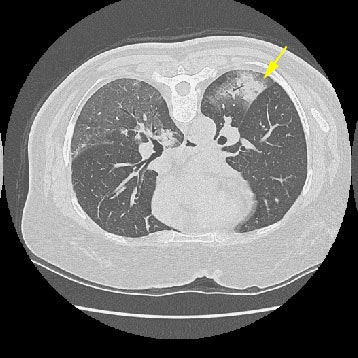

Ground Glass Attenuation: Suspected aspiration

The image below is from a HRCT scan performed in the prone position. There is diffuse ground glass attenuation within the right lower lobe which extends to the major fissure. Ground glass attenuation can also be seen in the left lower lobe. Additionally, there is an area of consolidation (yellow arrow) in the left lower lobe- consolidation obscures the underlying lung markings.